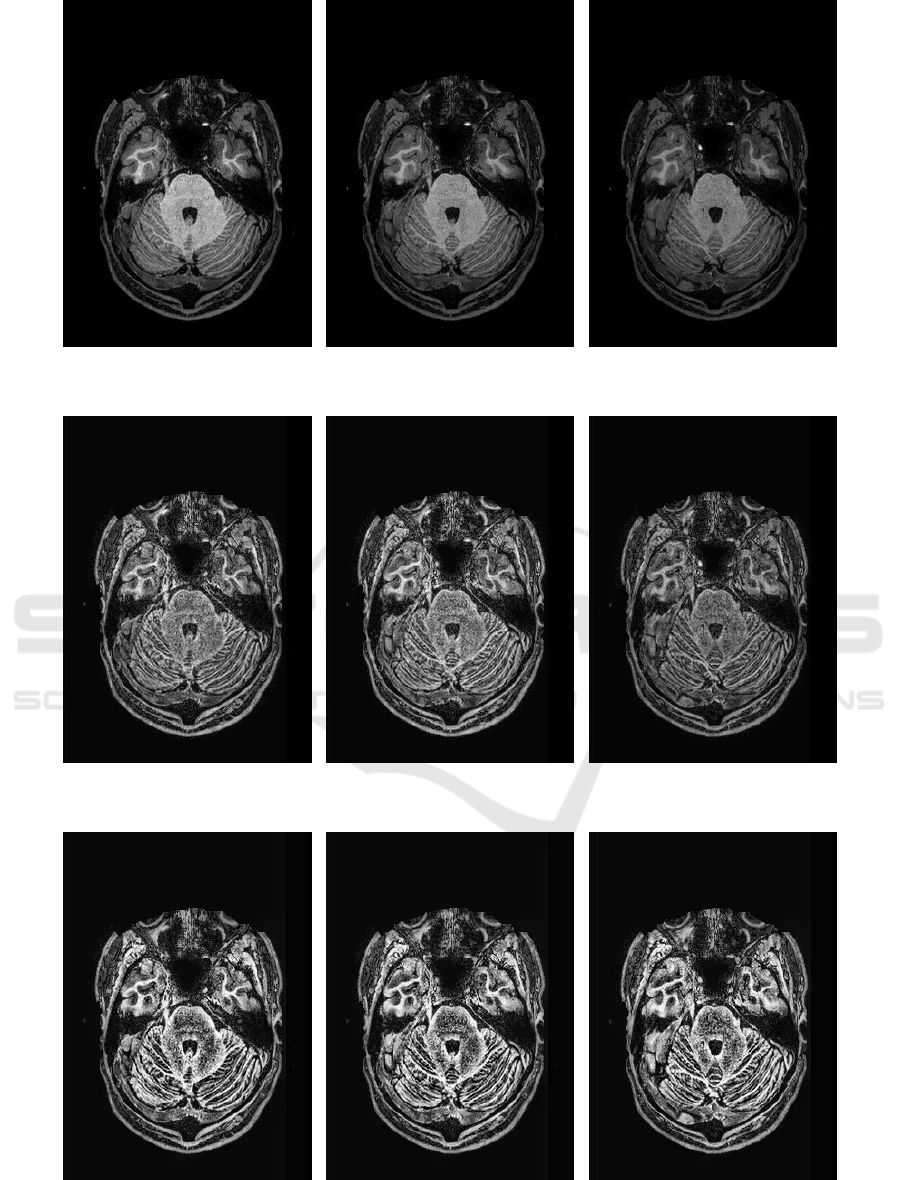

Marcus, D., Wang, T., Parker, J., Csernansky, J., Morris, J.,

and Buckner, R. (2007). Open Access Series of Imag-

ing Studies (OASIS): Cross-Sectional MRI Data in

Young, Middle Aged, Nondemented, and Demented

Older Adults. Journal of Cognitive Neuroscience,

19(9):1498–1507.